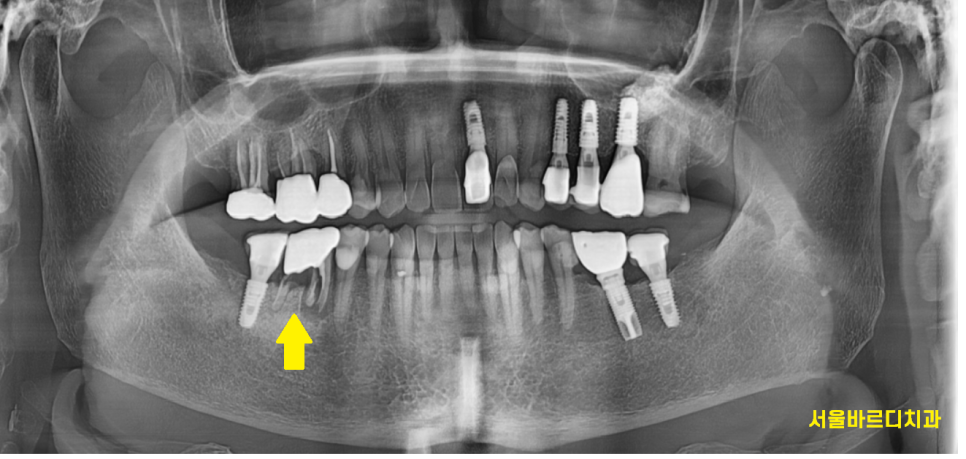

엑스레이 찍은 사진을 보고

오잉??

저절로 눈이 커졌는데요.

한눈에 보기에도 으스러진 치아들 ㅠㅠ

24.01.26

치아 뿌리 균열을 넘어

바스러졌습니다.

치아 뿌리 균열 상태에 비하여

뼈는 나쁘지 않아서

뽑고 암사동 치과에서 임플란트 바로 식립해드렸습니다.

ct에서 분석 했을 때

뼈가 좀 모자란 부분이 있어서

뼈이식도 함께 시행했는데요.

잇몸뼈가 부분적으로 녹은 부분이 있었습니다.

잇몸 앞쪽으로 뼈가 없다보니

임플란트 위치를 뼈가 많은 뒤쪽으로 심어드렸습니다.